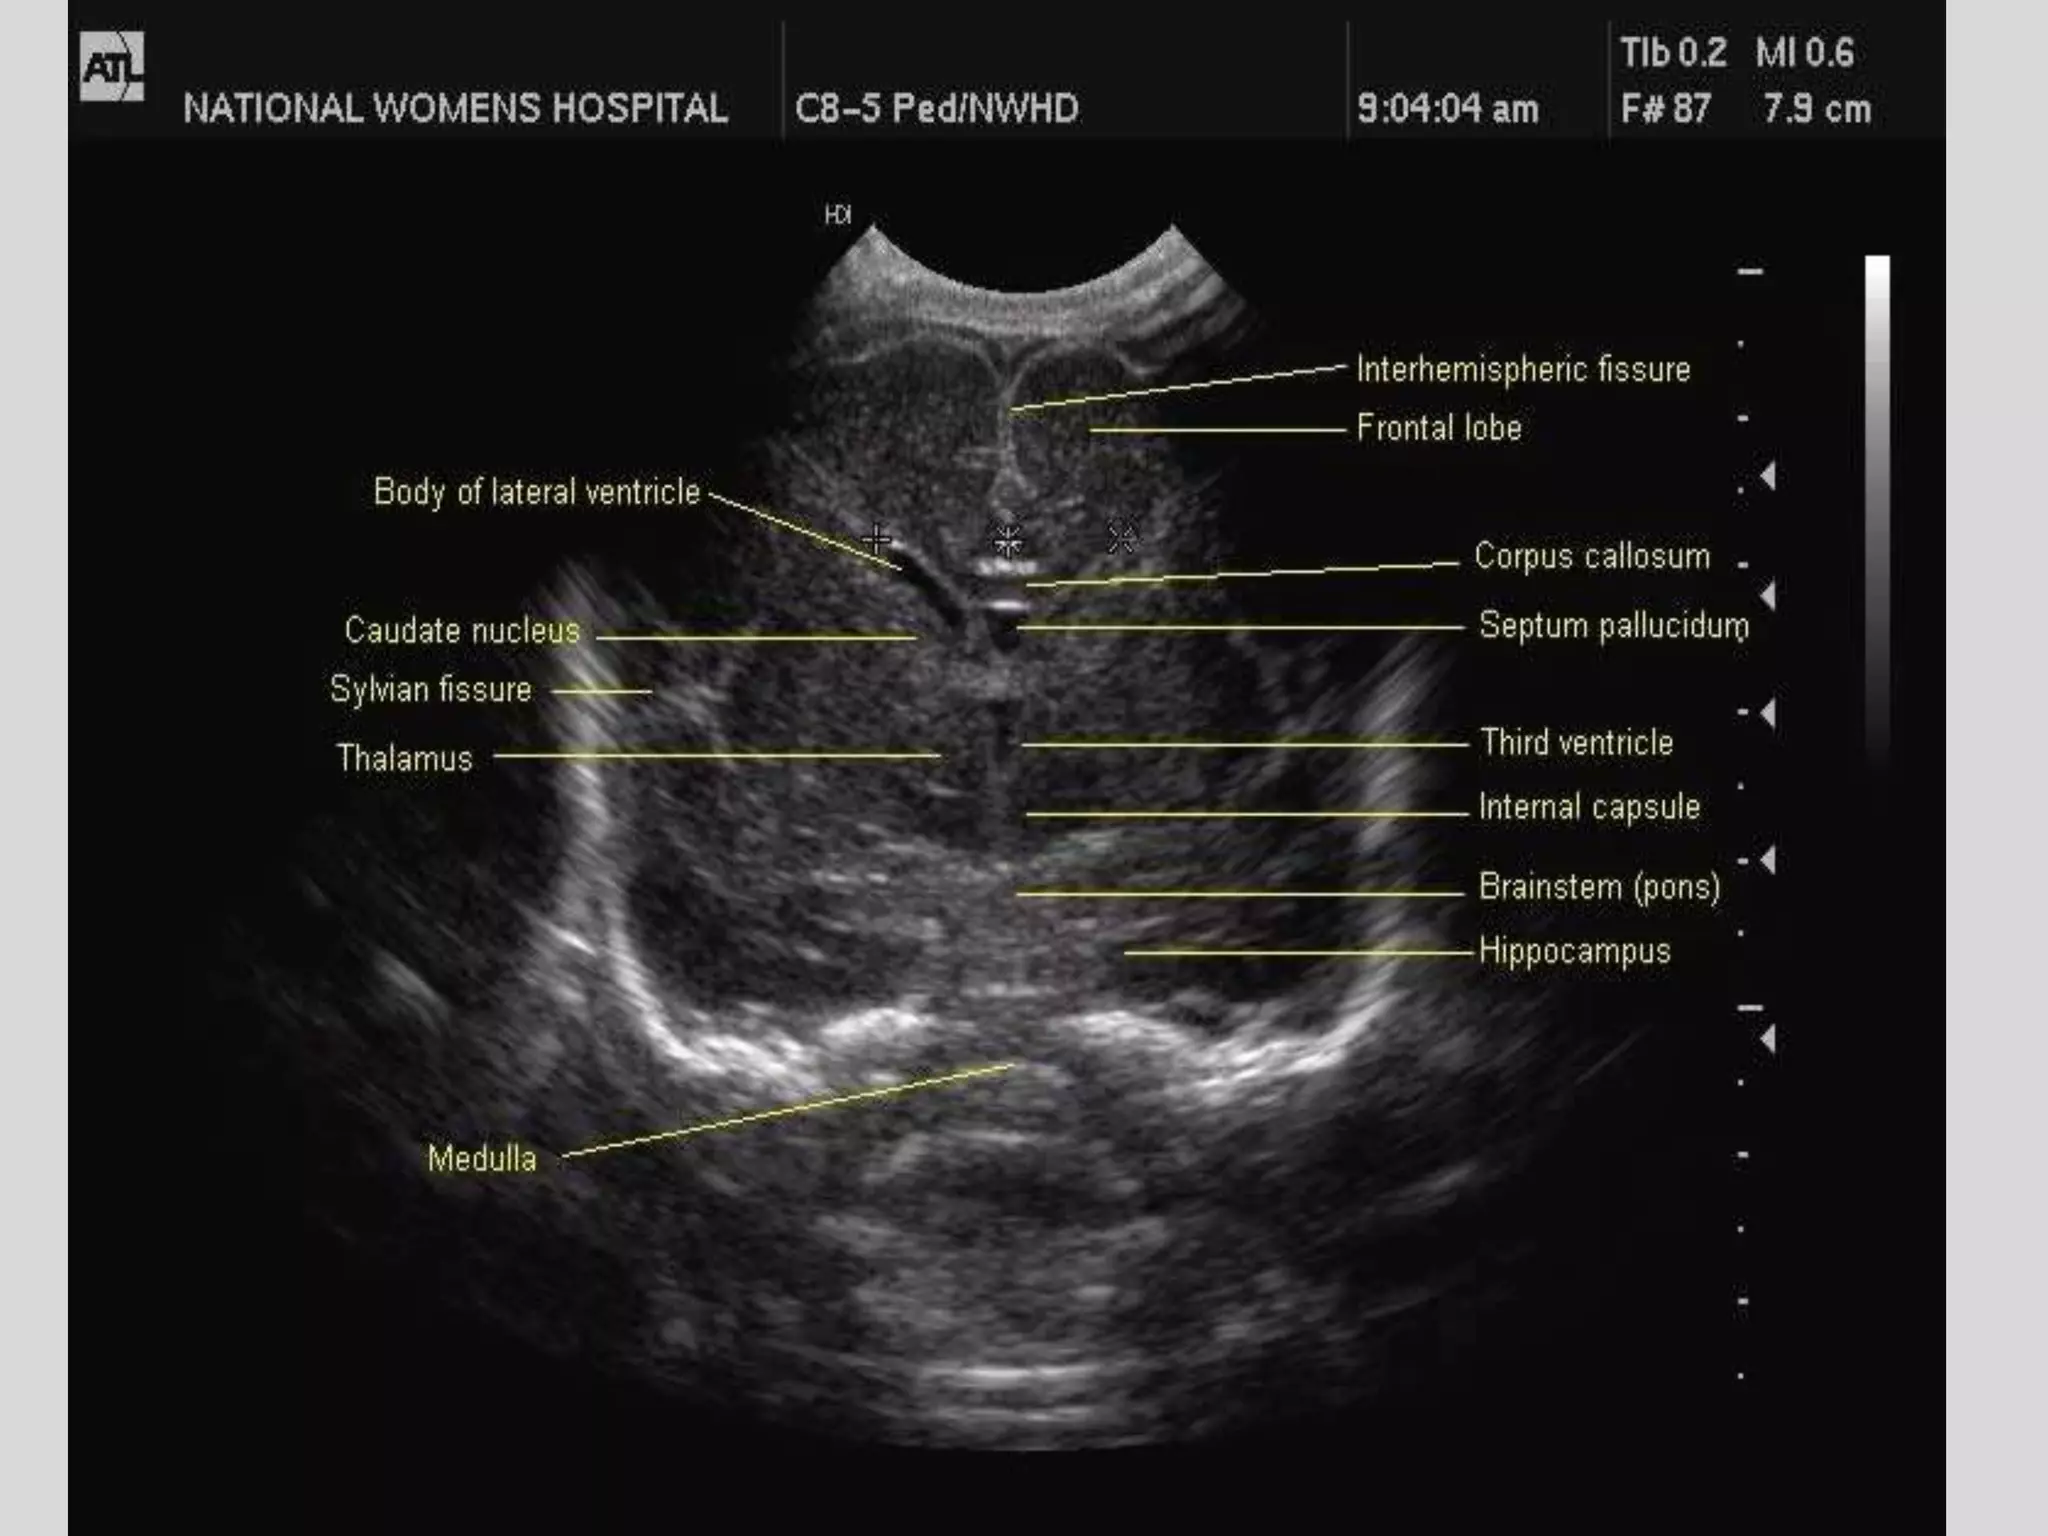

Cranial usg

Sagital view